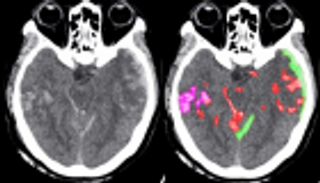

أكد مشاركون في مؤتمر دولي بدبي أن الاعتماد على تقنيات الذكاء الاصطناعي والروبوت في المجال الصحي سيحد من الأخطاء الطبية بنسبة كبيرة جدا، وسيسهم في إجراء الجراحات بدقة تقترب من 100%.

وأفاد متخصصون مشاركون في "المؤتمر الخليجي الثاني لتطوير كوادر الرعاية الصحية الرقمية" بأن تقنيات الذكاء الاصطناعي زادت من جودة القطاع الصحي في دول الخليج، ولفتوا إلى أنها تتيح الاكتشاف المبكر للأمراض أو توقعها قبل حدوثها، وتمكن من استشراف طرق العلاج وتوفير الرعاية الصحية الأفضل للمرضى بدقة متناهية.

وأصبح بإمكان الأطباء التنبؤ بأمراض القلب والإصابة بقصور في عضلة القلب من خلال فحص نبضة واحدة وبدقة 100% عبر برامج الذكاء الاصطناعي.